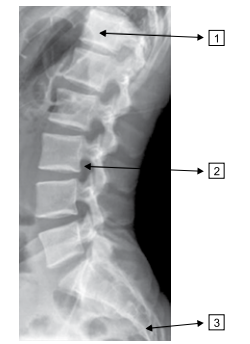

Quais regiões da coluna são assinaladas na imagem a seguir?